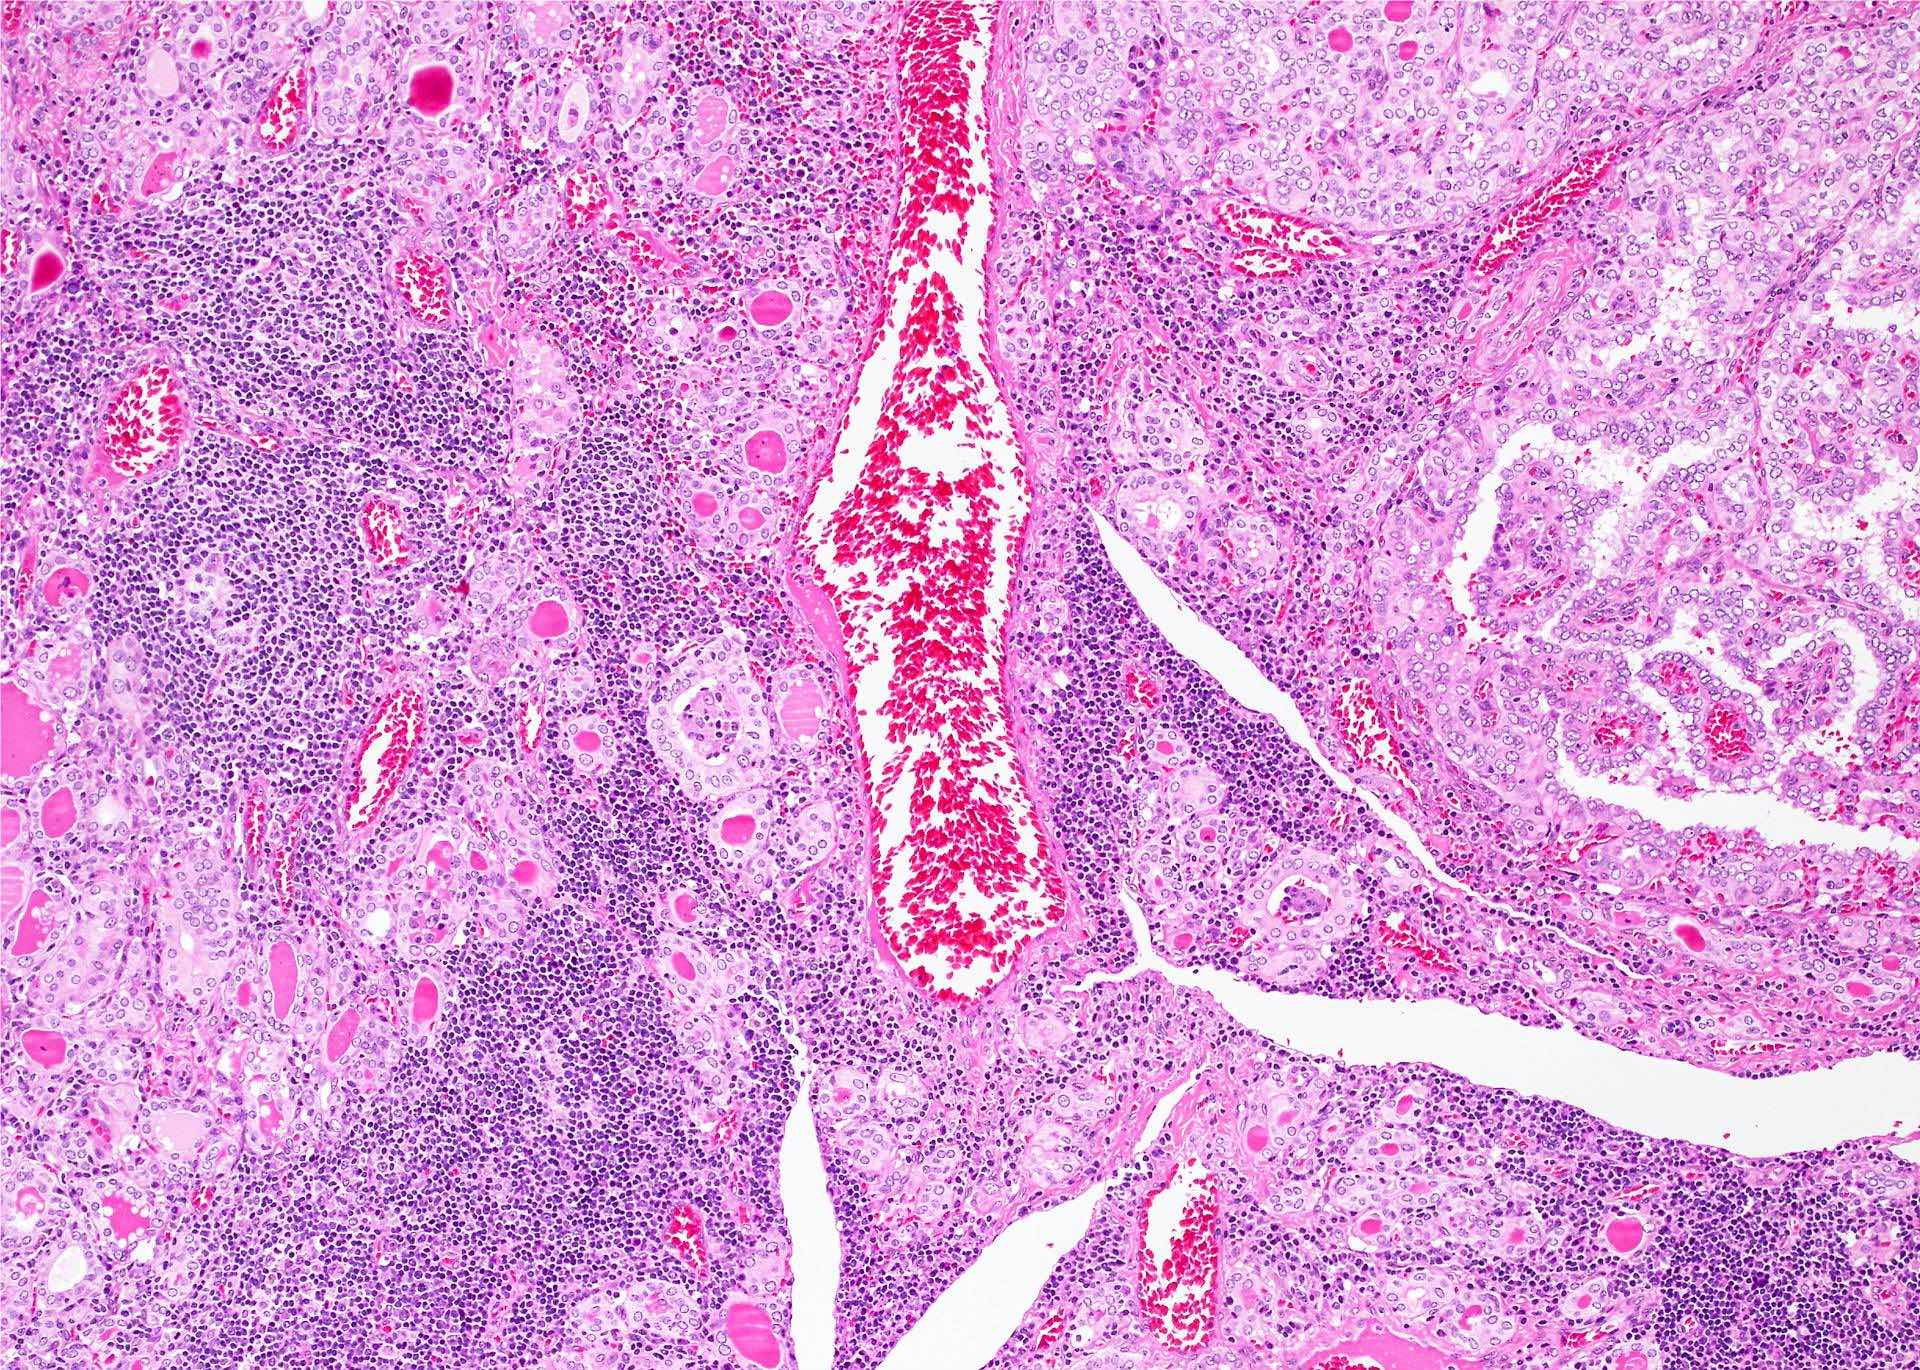

Microscopic (histologic) description

- Classic form: diffuse infiltration of thyroid parenchyma with lymphocytes and plasma cells; lymphoid follicle formation with germinal centers (Best Pract Res Clin Endocrinol Metab 2019;33:101367)

- Polymorphic lymphocytic infiltrate, predominantly T cells

- Thyroid follicular destruction

- Atrophic thyroid follicles; many lined by oncocytic cells / oncocytes having abundant granular eosinophilic cytoplasm; rarely squamous metaplasia

- Later fibrosis and nodularity (Virchows Arch 2013;462:557)

- IgG4 related variant: dense lymphoplasmacytic infiltrate, enriched in IgG4 producing plasma cells (> 20 cells per high power field); interstitial fibrosis; often associated with obliterative phlebitis (Autoimmun Rev 2014;13:391)

- May be associated with colloid goiter, follicular neoplasm, oncocytic cell neoplasm, papillary thyroid carcinoma and primary thyroid lymphoma (Acta Cytol 2009;53:507, Front Oncol 2017;7:53)

Microscopic (histologic) images

Contributed by Andrey Bychkov, M.D., Ph.D. and Shipra Agarwal, M.D.